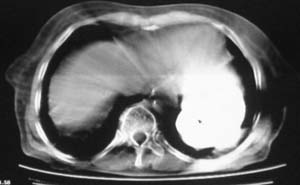

女,78岁,声嘶月余,否认有既往病史,有粉尘接触史10年。

颈部见多枚淋巴结肿大,考虑尘肺继发结核,喉部淋巴结钙化,不除外喉部慢性淋巴结炎、喉淀粉样变及类癌等

多考虑尘肺,肿瘤性病变不除外

尘肺合并肺癌。

肺癌伴纵膈、双颈部淋巴结转移;尘肺。

右上肺癌伴肺内转移及纵隔淋巴转移 左上肺结核 图像有点模糊

双上肺结节融合影,周围有纤维条索影,结合粉尘接触史,首先考虑尘肺。双侧颈部有增大淋巴结,有声嘶表现,肺癌淋巴结转移不能排除。可结合颈部淋巴结活检。